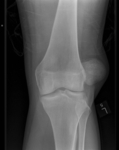

Radiografia do joelho esquerdo demonstrando luxação lateral da patela

Yerimah G, et al. BMJ Case Rep. 2013 May 2:2013:bcr2013009832; usado com permissão